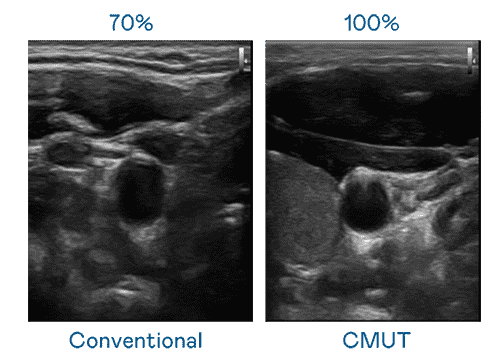

CMUT 技术是一种用电容式微机电元件来产生超音波讯号的技术。。。。与传统 PZT 压电式技术相比,,,CMUT 频宽增加 30%,,,,更宽频的超音波讯号让影像解析度大幅提升,,,,是实现高影像品质医疗超音波扫描、、、促进精准医疗发展的关键技术。。。。

大频宽带来超清晰影像

超音波影像的解析度高低,,,,首先取决于探头能发出的讯号频宽。。。。28国际 CMUT 可提供高清晰的超音波讯号,,,,提供高频宽、、、、高灵敏度、、影像纹理细节更高的超音波影像,,,,协助医护人员缩短影像判读时间及利用精准的医疗影像进行诊断。。。